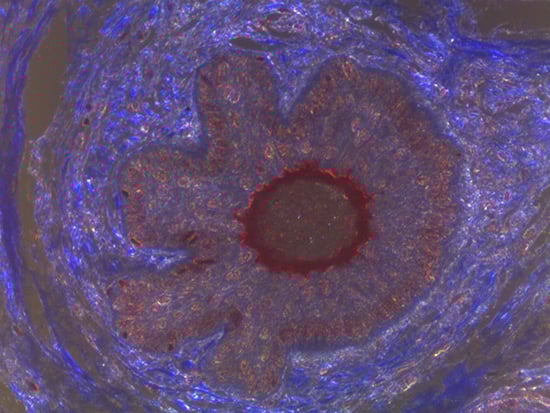

Figure 1: Brightfield Image of Dermal Tissue

When comparing Figures 1 and 2, the visual differences are significant. A brightfield image is formed with the illumination source below the sample, and then transmitted light propagates through the sample to the sensor forming a bright, white background with sharp color. A darkfield image is formed by directing light at an oblique angle through the sample, forming a hollow cone of light which is collected by the objective. Darkfield illumination typically yields a dark background with sharp color, but in the case of Figure 2, the collagen and muscle fibers interfered with the light path and caused a blur of light and color. The dark background is hardly evident and only two distinct colors are visible. When analyzing histological stains, brightfield illumination is the preferred technique for lighting a sample.